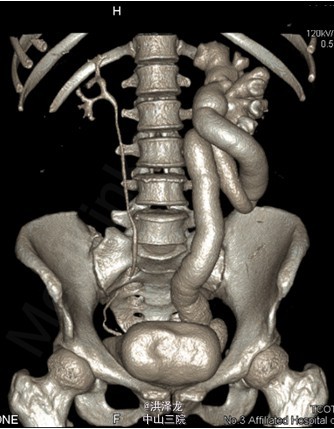

患者,女性,46岁。下腹胀痛半年。患者于6月前无明显诱因出现下腹部闷痛不适,无尿频、尿急、尿痛,无排尿困难,无血尿、脓尿,在当地医院行B超检查提示:左侧巨输尿管伴左肾 积液。现为进一步诊治收入我科。

双肾区无红肿、隆起,左肾区叩击痛(-),右肾区叩击痛(-),左侧肋脊点、肋腰点压痛(-),右侧肋脊点、肋腰点压痛(-)。腹平软,左侧输尿管走行区压痛(-),右侧输尿管走行区压痛(-),膀胱区无膨隆,压痛阴性。 CTU检查提示:左输尿管中段约平S1水平管腔稍变窄,其以下输尿管通畅,并进入膀胱内,其以上输尿管迂曲、扩张,扩张程度大致同前; 肾功能检查:左肾灌注正常,总体功能基本正常,左上尿路机械性梗阻

诊断:左侧巨输尿管。经术前准备后,行腹腔镜下左侧输尿管再植术,手术顺利,术后恢复较好。

现患者术后恢复良好,尿管已拔出,排尿正常,无腰痛、腹胀、腹痛等表现。成人巨输尿管的诊断主要依据影像学检查。治疗原则为解除梗阻,尽量保留患肾功能,应根据输尿管扩张程度选择输尿管折叠或裁剪加输尿管膀咣冉植术。肾功能良好、无明显症状者可保守治疗。